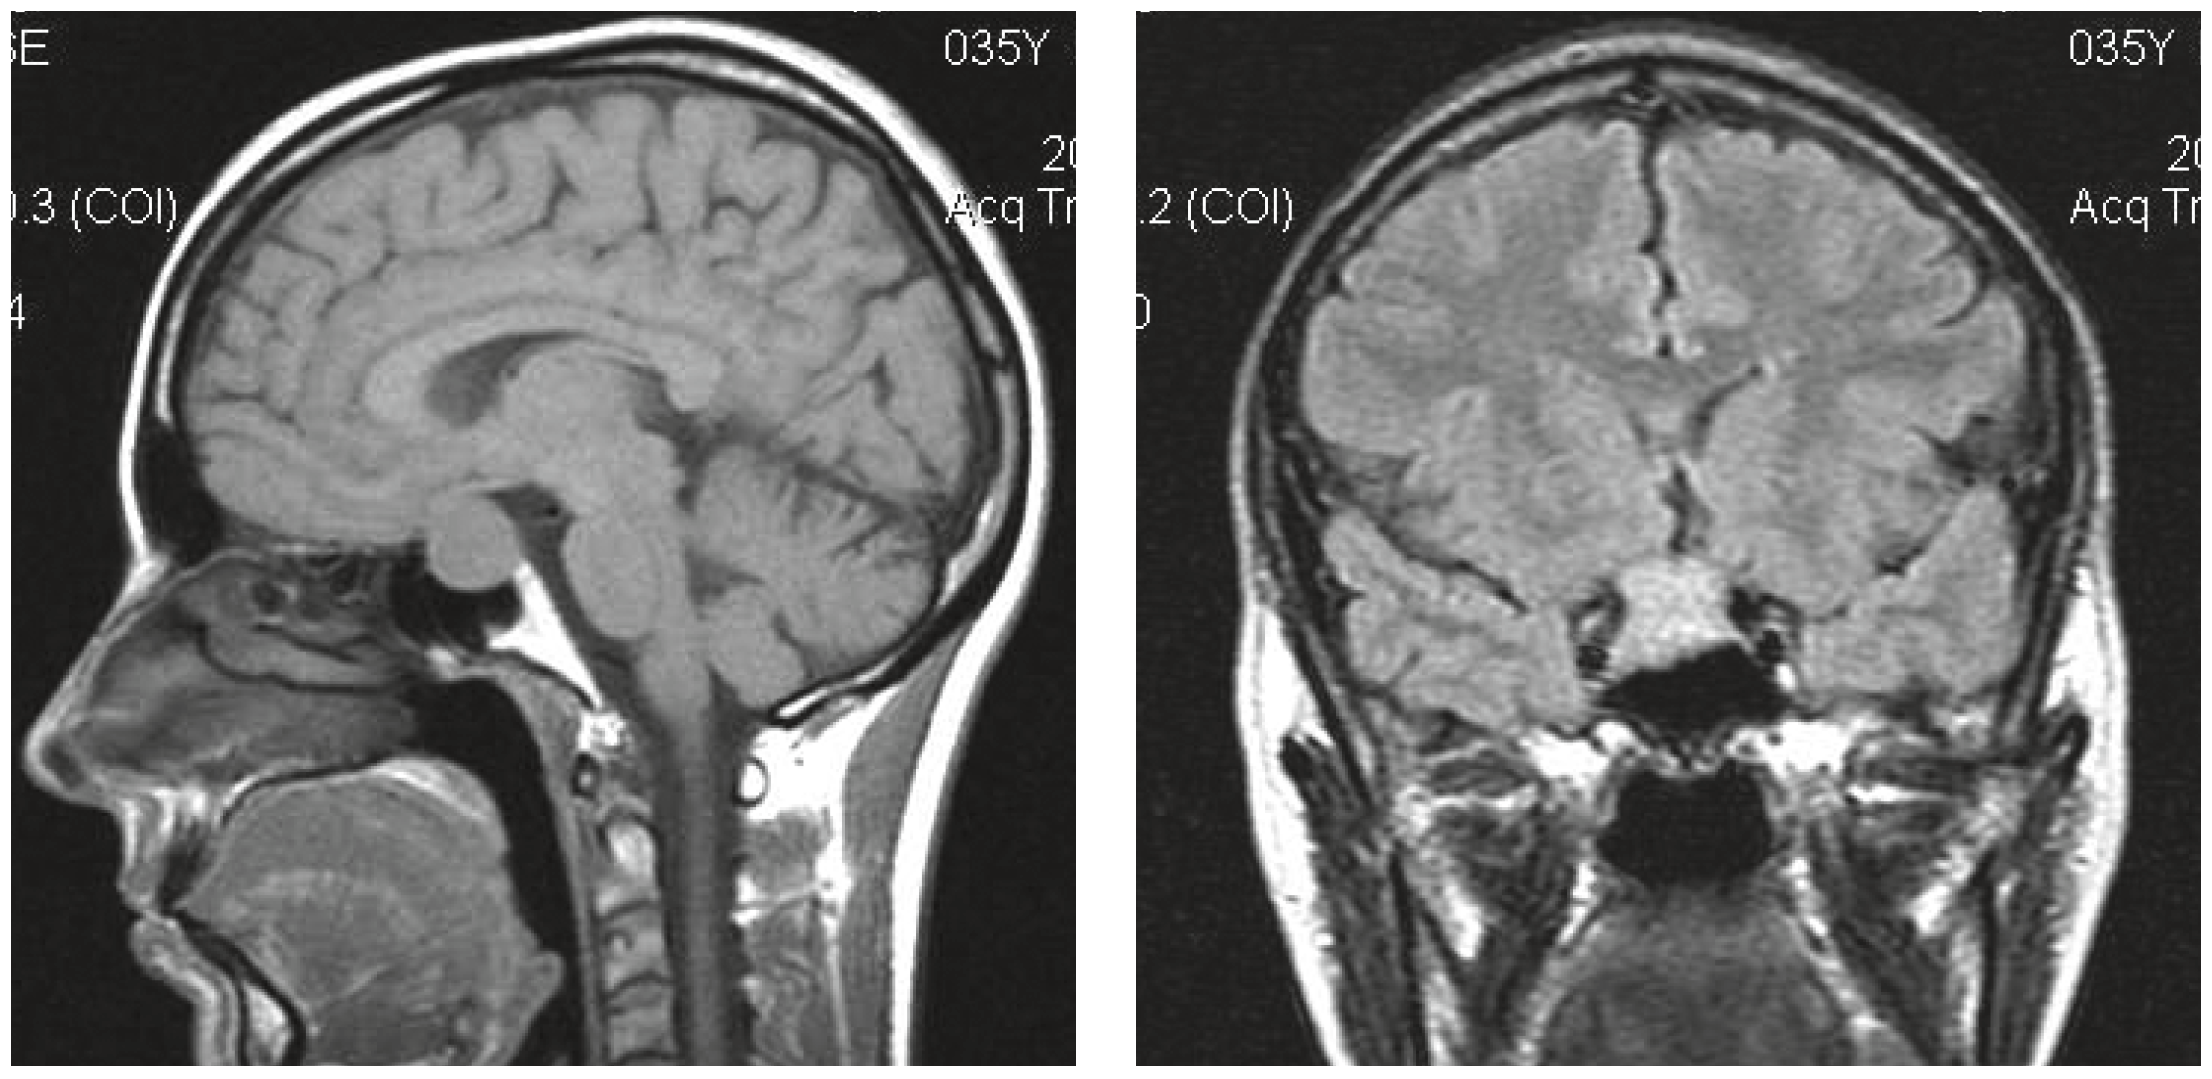

1. Fig. 1A. MRI of the patient's J. brain with pituitary adenoma before treatment | |

2. Fig. 1B. MRI of the patient's J. brain with pituitary adenoma during treatment | |